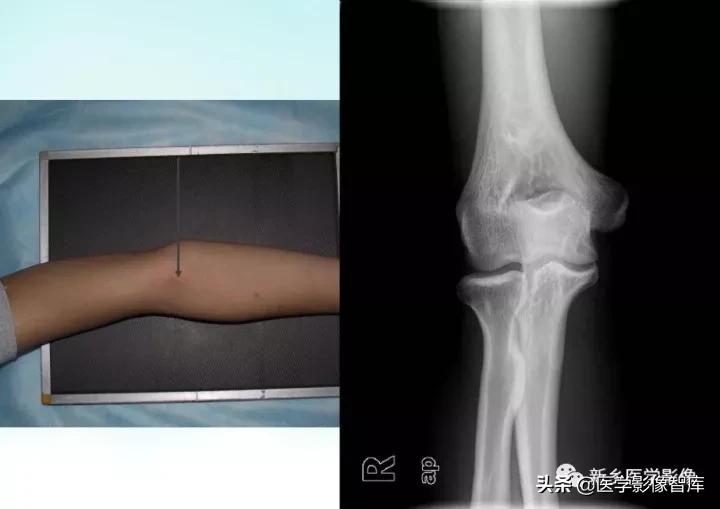

伸肘正位片上,肱骨、尺骨长轴线形成向外165°~170°的夹角,此为生理性前臂外翻角,男性一般大于女性。若小于l65°叫肘外翻,大于190°叫肘内翻,如果是180°则叫直肘(图1-1),均属异常表现。肱骨长轴与尺骨长轴在内下方的夹角谓之提携角,正常范围5°~20°之间,女大于男。